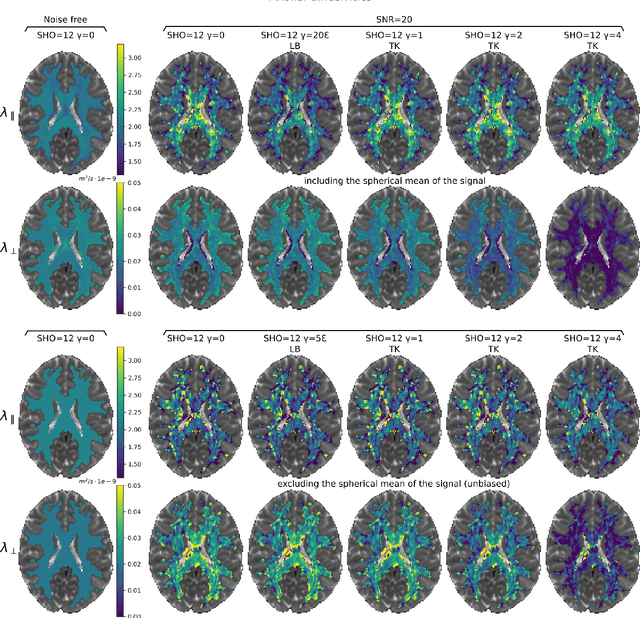

Abstract:We enable the estimation of the per-axon axial diffusivity from single encoding, strongly diffusion-weighted, pulsed gradient spin echo data. Additionally, we improve the estimation of the per-axon radial diffusivity compared to estimates based on spherical averaging. The use of strong diffusion weightings in magnetic resonance imaging (MRI) allows to approximate the signal in white matter as the sum of the contributions from axons. At the same time, spherical averaging leads to a major simplification of the modeling by removing the need to explicitly account for the unknown orientation distribution of axons. However, the spherically averaged signal acquired at strong diffusion weightings is not sensitive to the axial diffusivity, which cannot therefore be estimated. After revising existing theory, we introduce a new general method for the estimation of both axonal diffusivities at strong diffusion weightings based on zonal harmonics modeling. We additionally show how this could lead to estimates that are free from partial volume bias with, for instance, gray matter. We test the method on publicly available data from the MGH Adult Diffusion Human Connectome project dataset. We report reference values of axonal diffusivities based on 34 subjects, and derive estimates of axonal radii. We address the estimation problem also from the angle of the required data preprocessing, the presence of biases related to modeling assumptions, current limitations, and future possibilities.